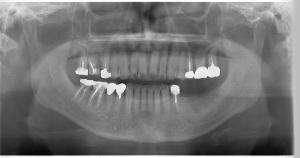

STEP1 カウンセリングと検査

STEP2 診断に基づいた治療計画の説明

治癒期間の目安上顎前歯/上顎奥歯:3~6ヶ月 下顎前歯/下顎奥歯:3ヶ月